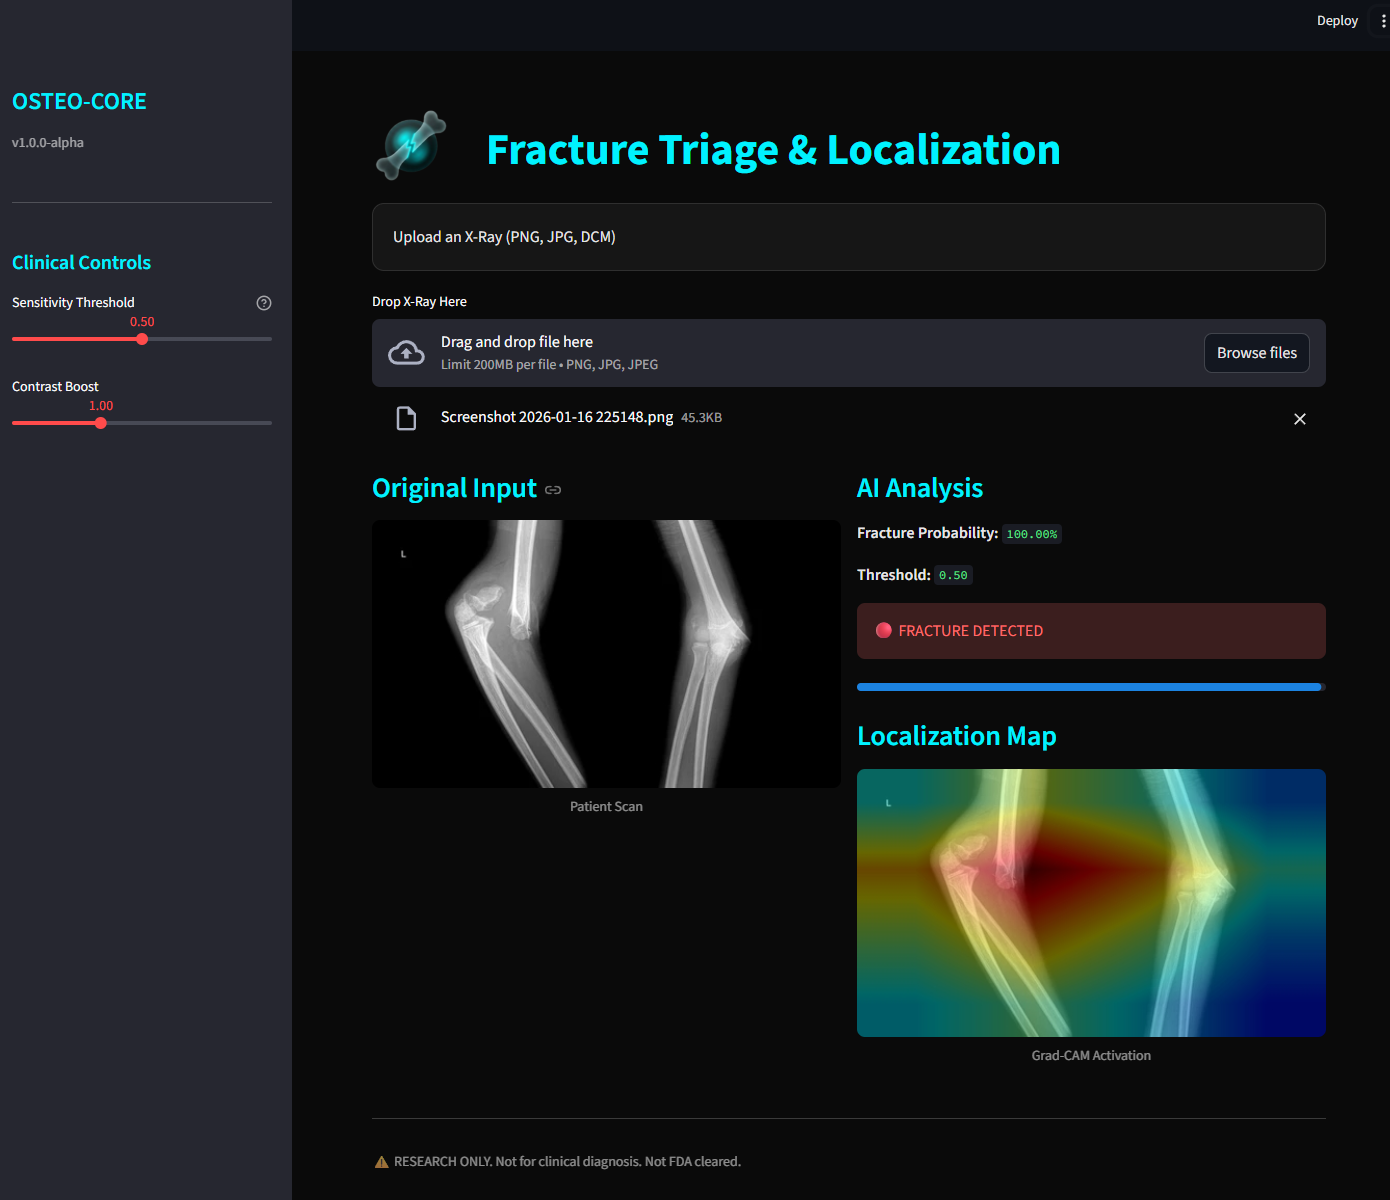

Weakly Supervised

Localization Maps.

OSTEO-CORE doesn't just classify; it identifies. Using Gradient-weighted Class Activation Mapping, the system highlights structural discontinuities in bone cortex that align with physical trauma.